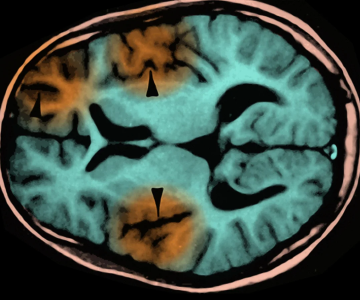

چالش درمان چاقی با سمگلوتاید

بیش از نیمی از کاربران داروی لاغری «سمگلوتاید» در کمتر از یک سال مصرف آن را قطع می‌کنند…